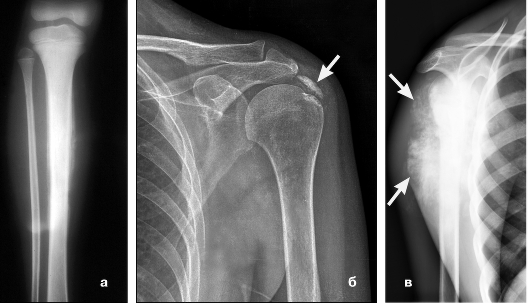

Диагностика заболевания

Чтобы установить точный диагноз, необходимо пройти ряд исследований:

- рентгенографию;

- магнитно-резонансную томографию (МРТ);

- компьютерную томографию (КТ);

- анализ крови для исключения или подтверждения инфекции.